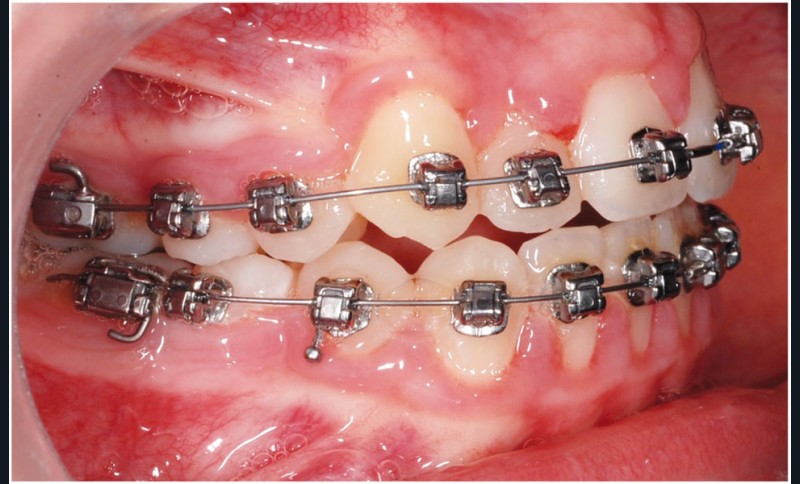

Le cas d’Anthony âgé de 11 ans et 7 mois qui présente une endomaxillie bilatérale associée à un léger encombrement mandibulaire dans un contexte de classe I squelettique hyperdivergente (fig. 1 à 10) est très représentatif de ce que peuvent apporter les forces légères appliquées aux alvéoles dentaires tout en intégrant des torques spécifiques qui permettent de contrôler parfaitement l’orientation radiculaire (fig. 11 à 29).

Le système laisse beaucoup de liberté dans l’interface entre bracket et arc : la vascularisation, et donc le recrutement cellulaire et la reconstruction osseuse s’en trouvent améliorés, la mise en place de l’occlusion se fait sous le contrôle de la matrice fonctionnelle, car les forces engagées restent en dessous de la puissance des forces masticatrices notamment.

Sans aucun appareillage d’expansion, le maxillaire a été transformé et semble avoir été soumis à une disjonction (fig. 30).